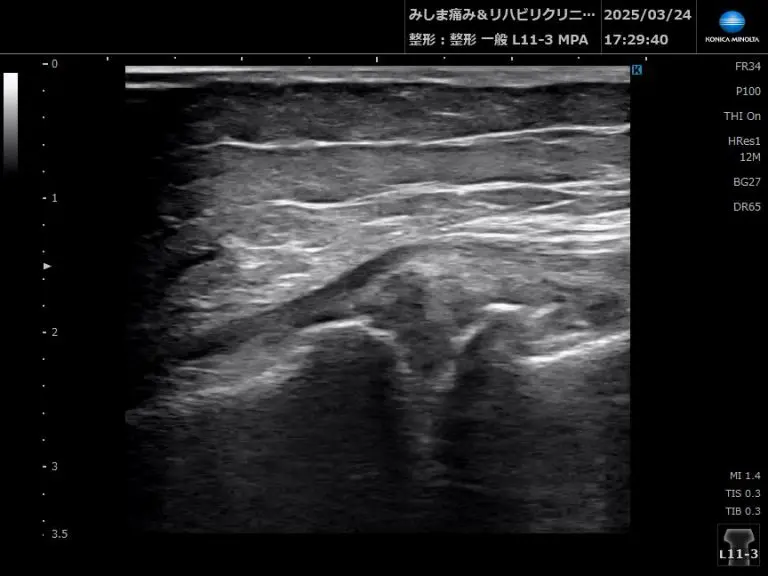

- 関節内構造の変性・破壊のチェック

→ 関節裂隙の狭小化や関節内の骨棘(骨化)などの変化。

- 半月板と骨棘をチェック